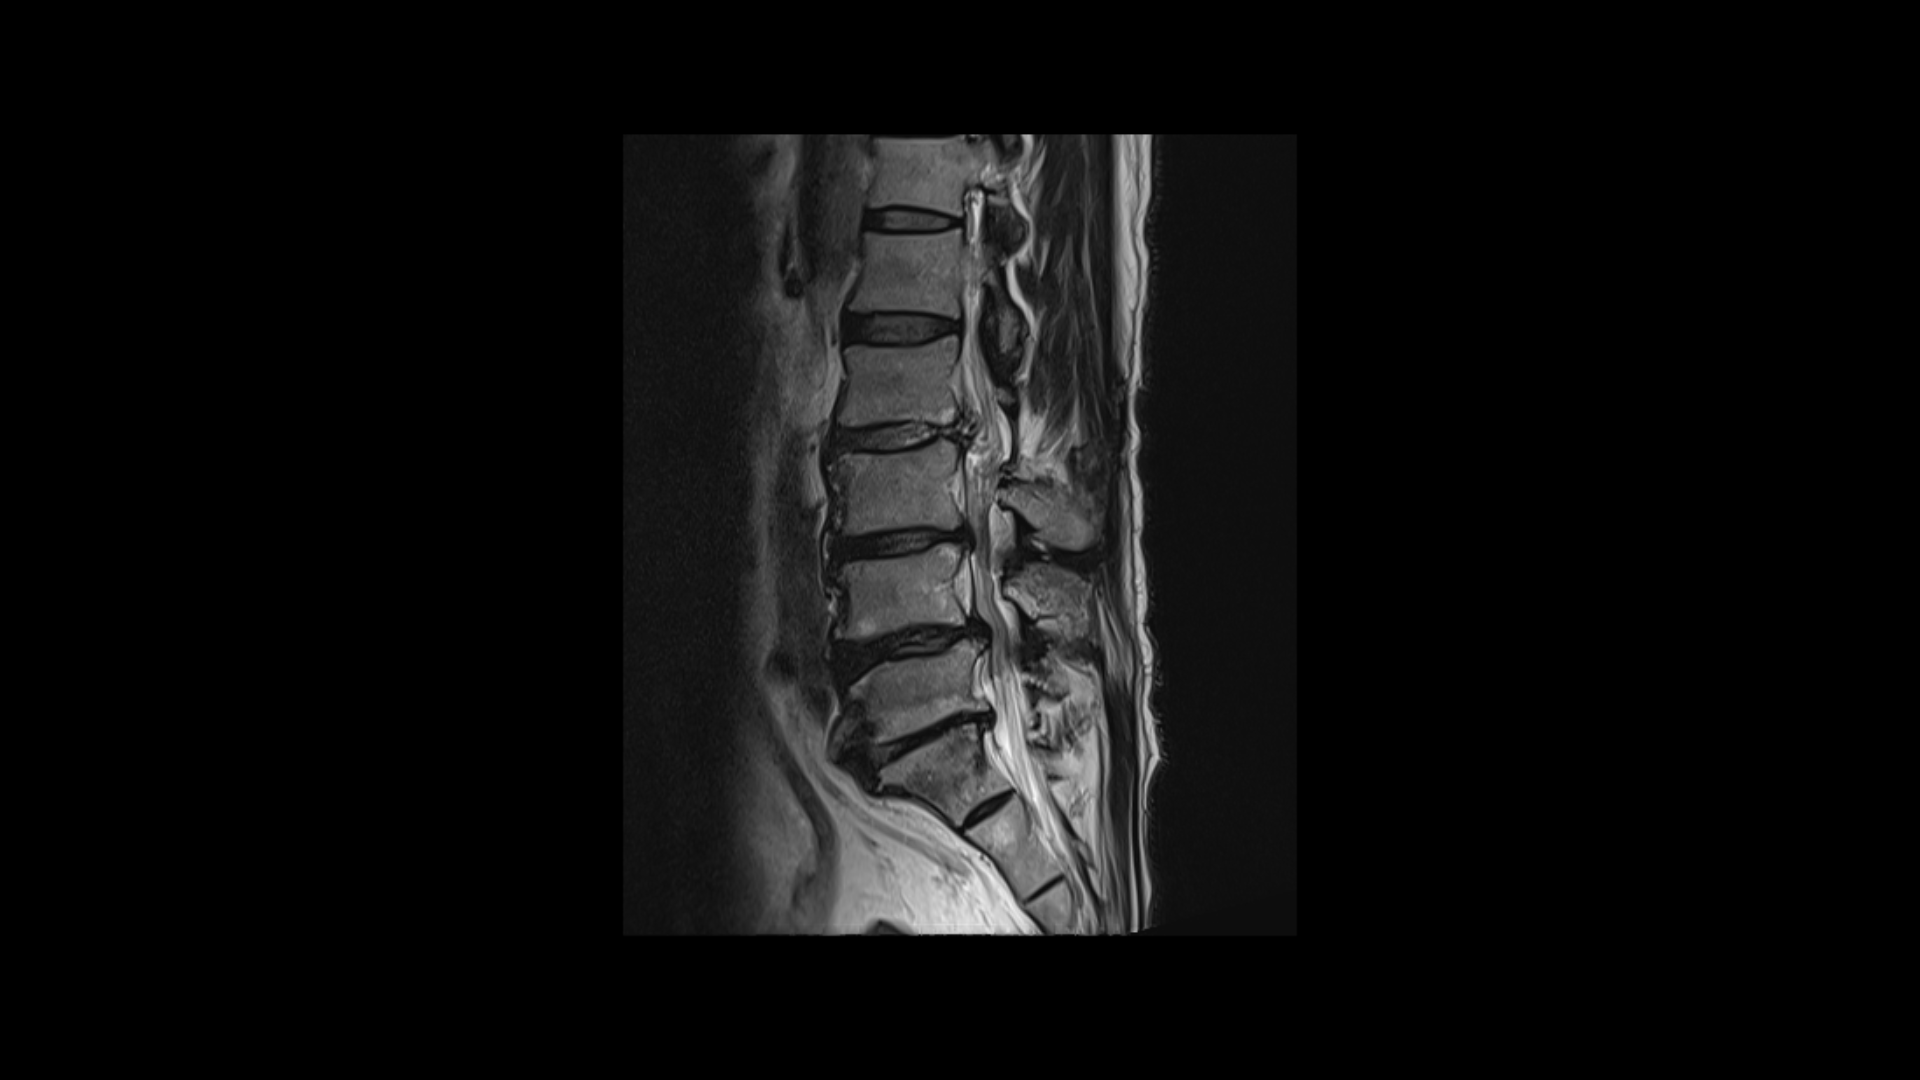

이분 MRI를 보면 네 마디에 퇴행성 디스크가 있고

두 마디에 중심성 협착이 있고

좌우로 나가는 신경구멍이 디스크와 협착으로 많이 좁아져 있습니다.

이분의 허리 MRI를 보면 2016년에 찍은 MRI와 2024년에 찍은 MRI가 있습니다.

이를 비교해보면 오른쪽, 왼쪽 다리의 마비 증상과 방사통의 원인인 걸로 추정되는 4번 5번과 5번 1번의 좌우 신경구멍이 비슷한 정도로 막혀 있습니다. 2016년과 2023년의 허리의 신경구멍이 좁아진 정도와 협착 정도는 비슷한 겁니다.